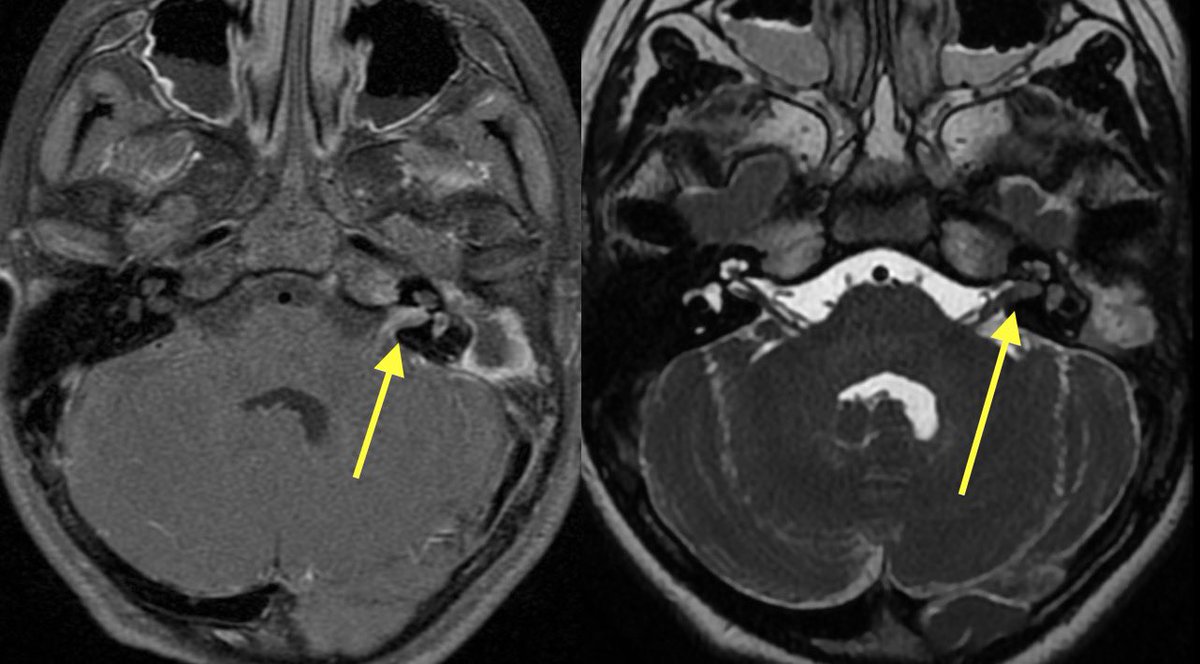

1️⃣DWI shows restricted diffusion of the left mastoid air cells (can be seen in cholesteatoma or purulent mastoiditis)

2️⃣However, additional restriction, enhancement, and loss of normal CSF signal in the left IAC was highly suggestive of suppurative Labyrinthitis

Cholesteatoma with superimposed infection was also complicated by meningitis (seen best at quadrigeminal plate cistern), ventriculitis, skull base osteomyelitis (petrous apicitis) and probably some other itisis that I’m forgetting